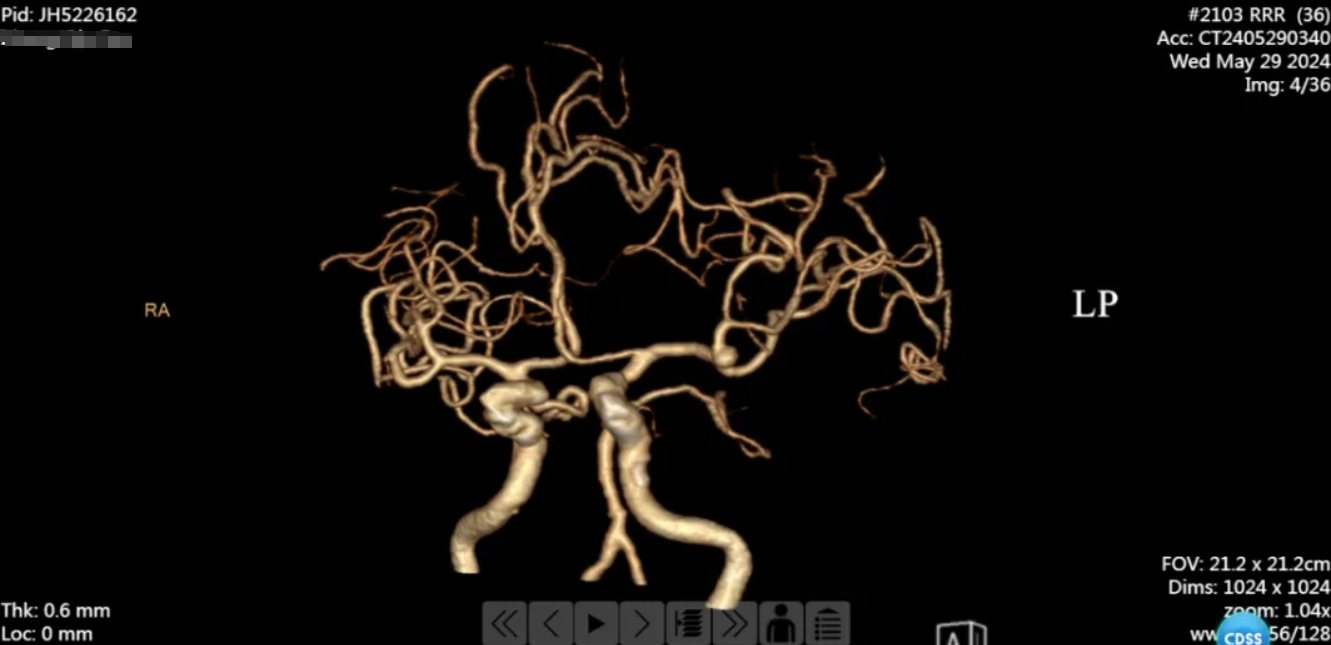

患者病情危重,被紧急转院至我院,经头颈部 CTA 后,医生诊断:

1、左侧大脑中动脉瘤破裂伴蛛网膜下腔出血

我院神经外科团队立即行动,予以对症治疗,同时,在征求患者家属同意后,决定为患者实施开颅动脉瘤夹闭术。时间就是生命,由汤明磊主任主刀,急诊在全麻下行左侧大脑中动脉瘤夹闭术。